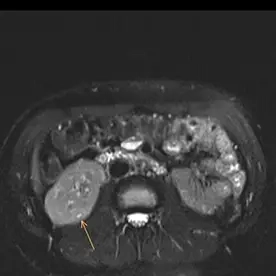

Es erfolgte eine MRT der Nieren mit intravenöser Kontrastmittelgabe und urographischer Phase zur dedizierten Darstellung der ableitenden Harnwege. Es bestätigte sich eine Anlagevariante der rechten ableitenden Harnwege, eine Doppelung des rechten proximalen Ureters mit Fusion im proximalen Drittel (Ureter fissus) bei regelrechter Darstellung der Nierenbeckenkelchsysteme (Bild 1). Im Nierenparenchym beidseits zeigen sich mehrere, keilförmige Areale mit Diffusionsstörungen und teils T2-hyperintensen Foci (Bild 2 und 3). Nach i.v. Kontrastmittelgabe zeigt sich ein weitesgehend unauffällig und homogen kontrastiertes Nierenparenchym beidseits (Bild 4).

Bild einer chronischen Pyelonephritis i.R. einer rezidivierender Reflux auf dem Boden eines Ureter fissus.